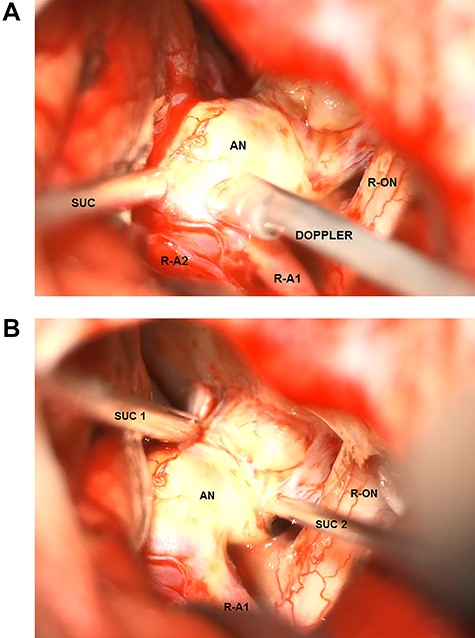

After pterional craniotomy on the right side, the anterior vasculature, optic nerves and chiasm were dissected, and all perforating vessels were preserved. The anteriorly directed part of the aneurysm was massively calcified, even ossified and adhered to the skull base at the level of the tuberculum sellae (see Fig. 2A and B). Thus, separating the aneurysm from the anterior skull base was not possible. The right A1 segment was temporarily clipped. The flow inside the aneurysm was assessed by means of micro-Doppler examination that showed a preserved intensive perfusion signal from the left side (Fig. 2B). The aneurysm was further dissected, but the right A2 segment could not be separated from the bulky, rigid aneurysm sack. Compression of the aneurysm was also not possible, and no clip could be positioned because of massive calcification of the aneurysm wall (Fig. 2A). After circumferential dissection and consecutive identification of all vessels as well as repeated attempts to compress the aneurysm and to restrain the flow, surgery was finally discontinued because of the increasing risk of aneurysm rupture in the case of further manipulation.

Intraoperative microscopic transsylvian view of the aneurysm. (A) Intraoperative microscopic transsylvian view of the aneurysm after the failed attempt to compress the calcified aneurysm with two suction devices (AN = aneurysm, R-ON = right optic nerve, SUC = suction, and R-A1 = right anterior cerebral artery). (B) Intraoperative microscopic transsylvian view of the aneurysm showing the assessment of the flow inside the aneurysm by means of micro-Doppler examination after temporary clipping of the right A1 segment. (AN = aneurysm, R-ON = right optic nerve, SUC = suction, DOPPLER = micro-Doppler, R-A1 and R-A2 = right anterior cerebral arteries).